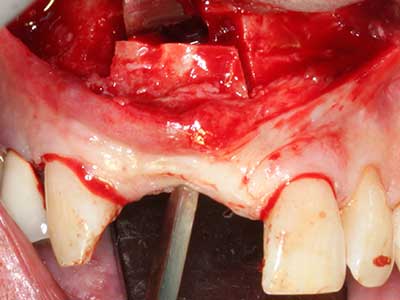

La piezochirurgia presenta altri vantaggi per quanto riguarda la raccolta di blocchi ossei. Oltre all'elevata precisione dell'osteotomia appena descritta, l'utilizzo di puntine per sega molto sottili permette di minimizzare in maniera significativa la perdita di materiale. È molto probabile che si verifichi una maggiore perdita di materiale durante la raccolta utilizzando puntine di strumenti più spessi, in particolare delle frese Lindemann (Lakshmiganthan, Gokulanathan et al. 2012). La separazione basale, necessaria in particolare per i trapianti di blocchi nella zona retromolare, viene semplificata grazie a seghe specificatamente progettate di forma rettangolare; di conseguenza la piezochirurgia è considerata una procedura precisa, semplice e sicura per la raccolta di blocchi di osso nella zona retromolare (Happe 2007) (figg. 1-12).